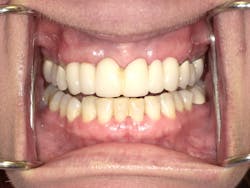

Karen returned, and under conscious sedation the dentist removed the existing bridge and placed implants as planned. An interim temporary bridge was constructed to get her through the healing process and until abutments would be placed. In the meantime, individual crowns were completed on Nos. 3, 4, and 5. Shortly thereafter, crowns were completed on the left side on teeth Nos. 12, 13, and 14. She is currently awaiting the final implant supported bridge on Nos. 6–8 and 9-11.

It goes to show: as professionals, what may often be routine for us is a life event for many patients. Getting past her anxiety and establishing value and trust was imperative for her to feel comfortable enough to complete a very expensive and time-extensive treatment plan. Karen doesn’t come across as anything but your average middle-class citizen, but she saw the value to and had the desire to replace a failing restoration and improve her smile and self-confidence. It goes to show you can’t judge a book by its cover.